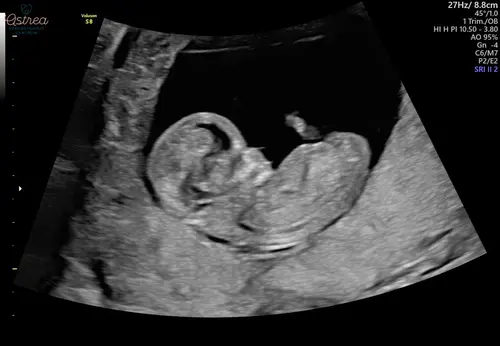

En wat denken jullie op basis van deze echo? 😀

Ik denk een jongetje